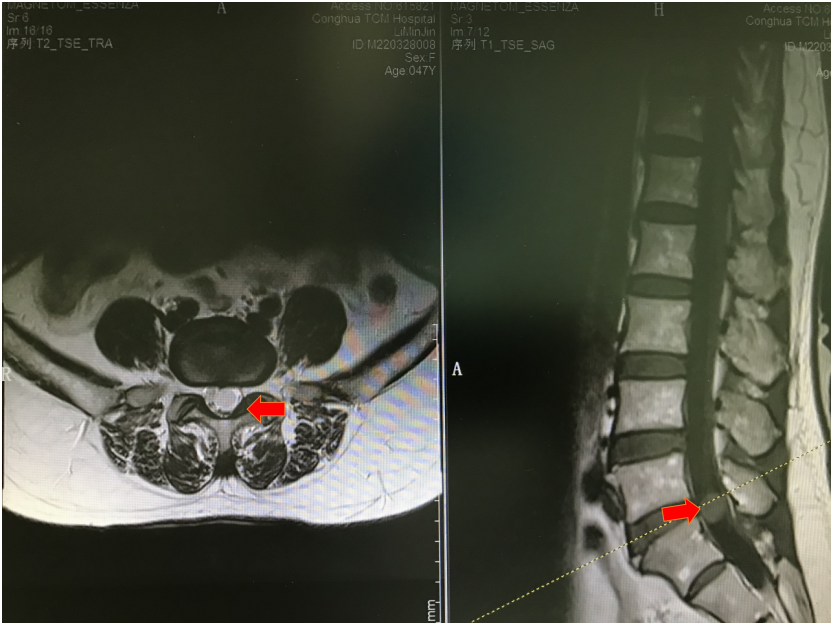

根据MRI检查结果,李女士腰5/骶1椎管内有一个玻璃弹珠大小的肿物,马尾神经严重受压,排除腰椎间盘突出诊断,椎管内肿瘤诊断明确。肿瘤强化不明显,说明肿瘤血运不丰富,跟椎管内胆脂瘤比较相符,但最终需要病理结果证实。目前诊断已基本明确,手术指征也是明确的,它就像一颗定时炸弹,如果不及时拆除,症状随时可能加重,严重者甚至会导致大小便失禁等马尾神经损伤的症状。

腰椎MR/ 提示椎管内巨大肿物压迫马尾神经

腰椎MR增强/ 考虑实质肿瘤,性质待定